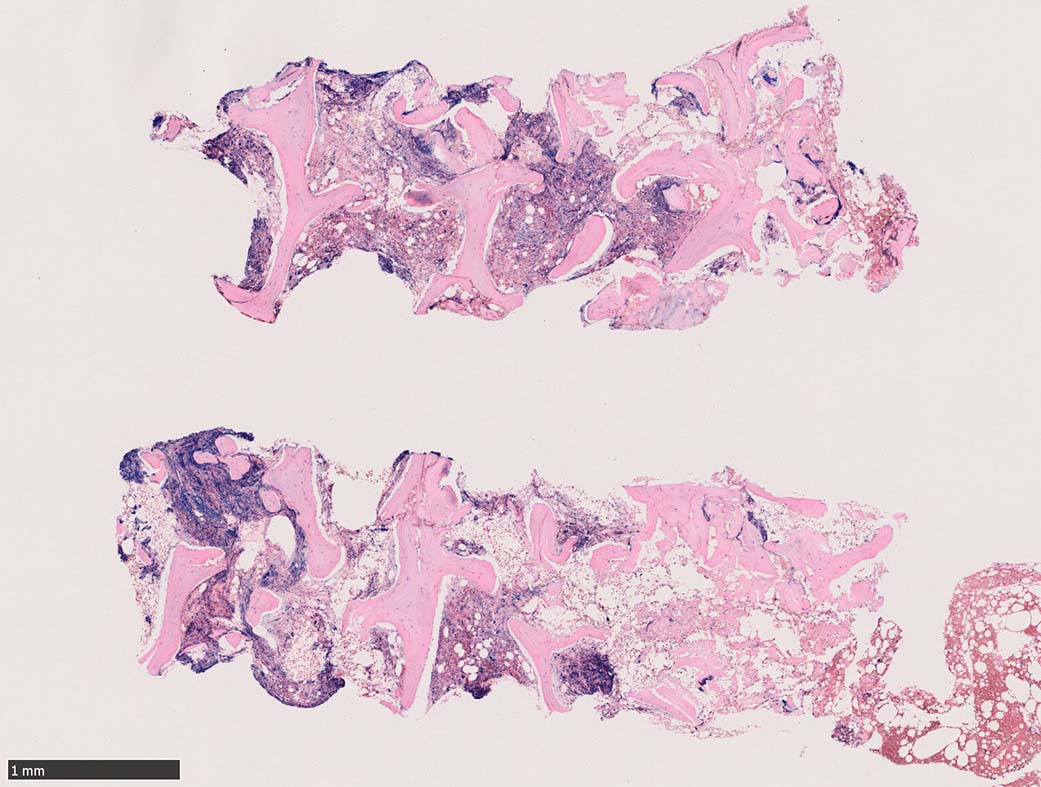

骨髄組織所見 bone marrow biopsy total 6mm in length

塗銀染色

Case02; Meylofibrosis, overt fibrosis

黒染する弾性線維の増生のほか, 赤く染まる膠原線維の増生が確認される. MF-2 fibrosis. 鍍銀染色の核染色をすると膠原線維の赤染がわからなくなるので行わない.